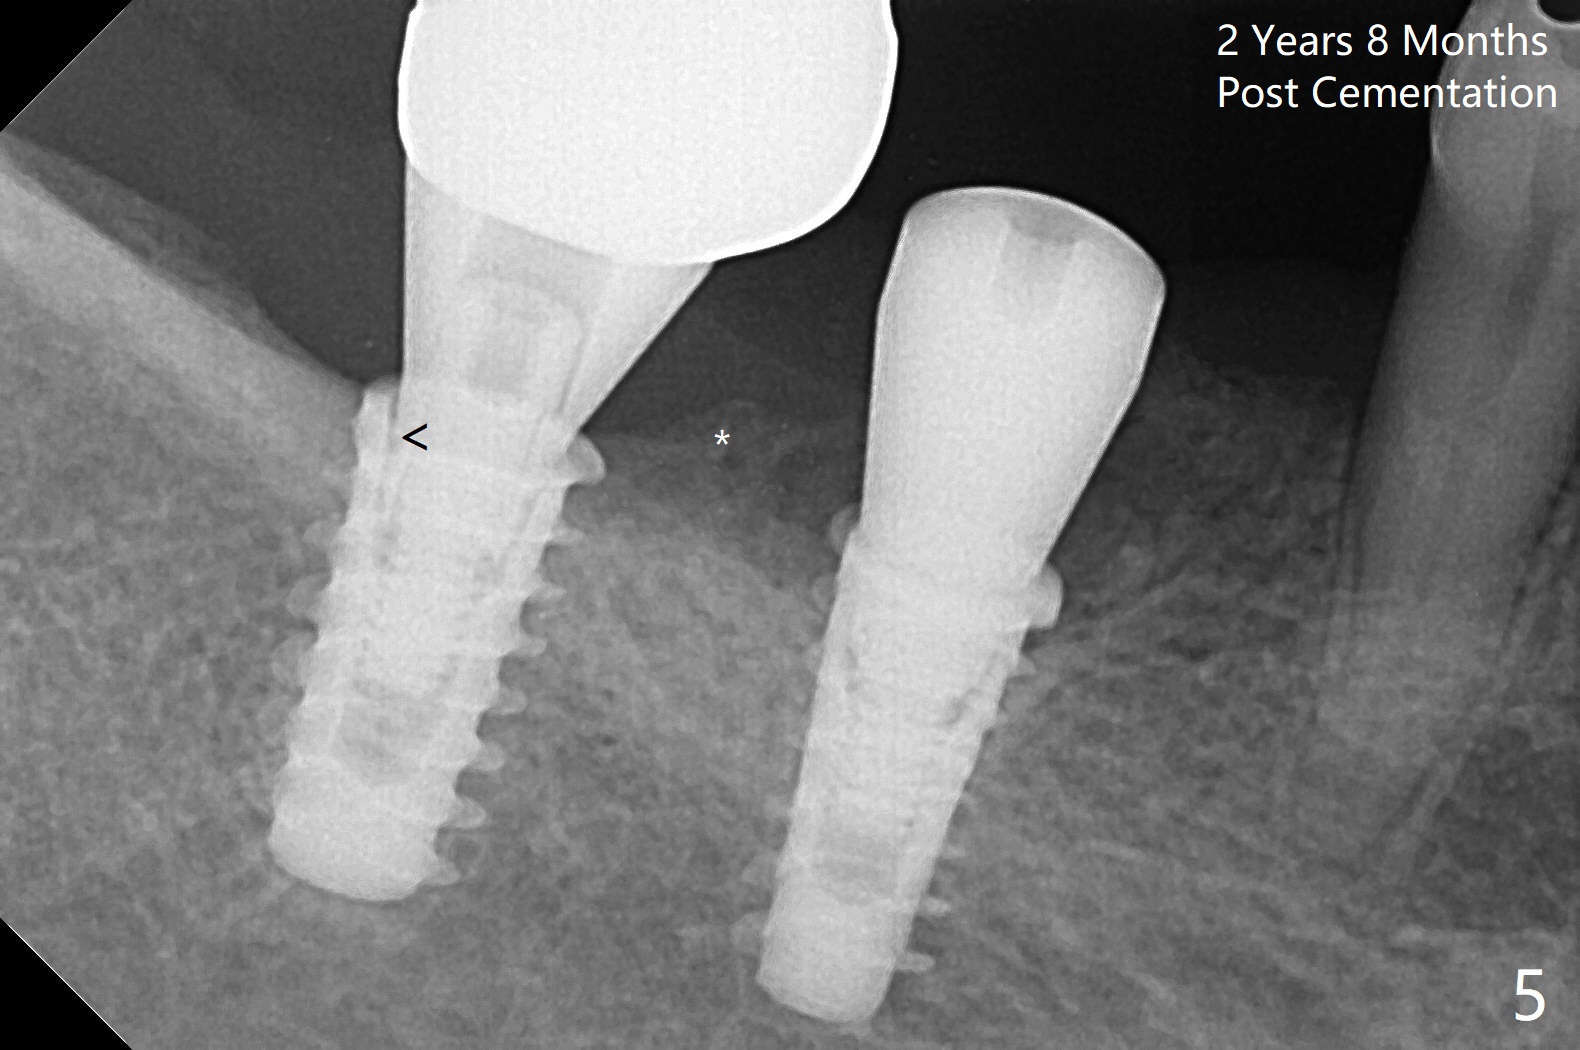

Following osteotomy, 4.5x11 and 5x9 mm dummy implants are placed at the sites of #30 and 31, respectively (Fig.1). Due to limited inventory of Magicore and patient's in-cooperation, FC implants (4.5x9 and 5x9 mm) are placed (Fig.2). A healing abutment (6x4 mm) is placed at #31 because of low torque (overprep), while a pair abutment (6.5x5.7(4) mm) is placed at #30. Vera Graft is placed with autogenous bone (*). The implant/abutment ratio at #30 is unfavorable. If the implant turns out to be loose, immediate implant should be larger in the future. Note bone growth, especially at #30, 2.5 and 4 months postop (Fig.3,4). In fact the abutments are incompletely seated. The crown of #30 is loose 2 years 8 months post cementation, while the abutment at #31 remains incompletely seated (Fig.5). The latter is completely reseated after separating the crown, while a smaller one is seated at #30 (Fig.6) due to use of a small healing abutment earlier (Fig.5). A good piece of news is the presence of the bone between the implants (Fig.5,6 *), which contributes to interimplant papilla. Return to Lower Molar Immediate Implant, Prevent Molar Periimplantitis (Protocols, Table), IBS77, 2-5 Xin Wei, DDS, PhD, MS 1st edition 09/22/2017, last revision 12/01/2020